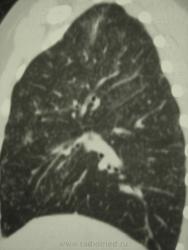

девушка 1985 г.р. дообследована после профилактической флюорографии, на КТ написали гистиоцитоз. Диагноз пока не подтвержден. Жалоб не предъявляет, курит в течение 8-9 лет. консультирована у фтизиатров, свою патологию они исключили.

На мой взгляд, выражены два компонента:

- преимущественно мономорфная диссеминации;

- интерстициальный компонент.

По рентгенограммам, создается впечатление превалирования "изменений", преимущественно, в средних и нижних отделах легочных полей.

Но, КТ, по всей видимости, свидетельствует, именно, о диффузности процесса, с некоторым превалированием в отдельных отделах.

Изменения диффузны. По rg более выраженны в нижних отделах, за счет марсива тканей. Ждем анализ мокроты и промывных вод.